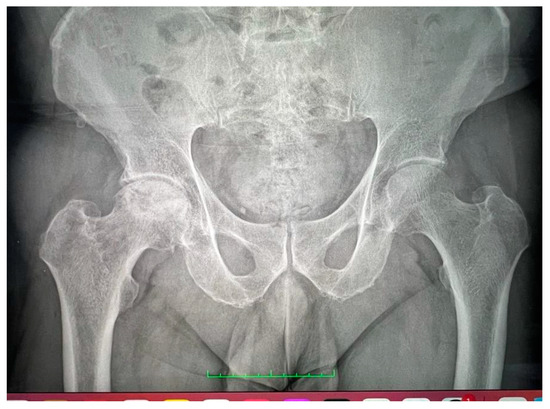

By adhering to stringent inclusion criteria and rigorous diagnostic standards, we sought to enhance the accuracy and validity of our analysis. This meticulous approach not only bolstered the credibility of our findings but also facilitated a comprehensive exploration of the intricate relationship between COVID-19 and avascular necrosis of the femoral head (Figure 1 and Figure 2).

Figure 2. Bilateral X-ray with avascular necrosis.